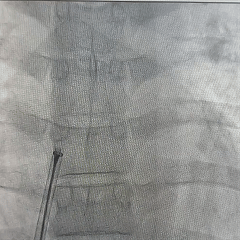

DSA下左盘展开

左盘面贴靠房间隔

DSA下牵拉试验

验证封堵器稳定夹持于缺损处

DSA下逆时针旋转解脱钢缆,释放封堵器